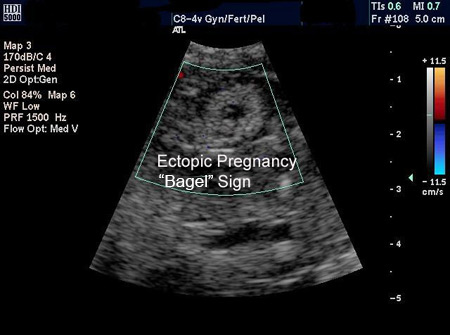

A gravidez ectópica é visualizada na USTV, e o diagnóstico é feito de maneira direta.[Figure caption and citation for the preceding image starts]: Imagem de ultrassonografia de gravidez ectópica demonstrando sinal de "rosquinha"Do acervo da Dr. Melissa Fries; usado com permissão [Citation ends].

[Figure caption and citation for the preceding image starts]: Imagem de ultrassonografia de gravidez ectópica demonstrando sinal de "rosquinha"Do acervo da Dr. Melissa Fries; usado com permissão [Citation ends].

Uma massa anexial movendo-se separadamente para o ovário, às vezes chamada de "sinal deslizante", com um saco gestacional vazio, às vezes descrito como um "anel tubário" ou "sinal em forma de anel", e uma massa anexial complexa, não homogênea, movendo-se separada para o ovário, são altamente sugestivos de uma gravidez ectópica, mas não diagnóstico.[62]